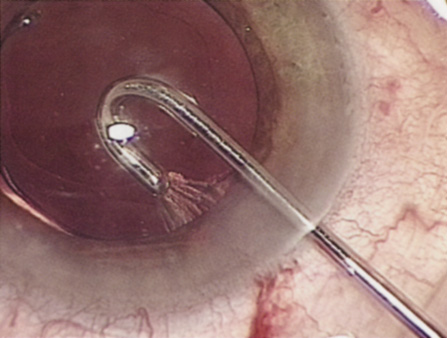

CLEAR CORNEAL AND NEAR-CLEAR CORNEAL INCISIONS

When constructing a clear corneal incision, the external aspect of the incision is either at the limbus or slightly anterior to the limbus, offering several advantages. First, a conjunctival flap is not necessary and bleeding is minimal, making a clear corneal approach favorable for patients with bleeding tendencies. Patients undergoing topical anesthesia will be more comfortable during surgery because they do not have to endure the discomfort that cautery can cause. Because a conjunctival flap is not necessary, patients are less likely to have discomfort that can develop from roughness at the conjunctival incision. Patients who have a functional filtering bleb or in whom conjunctiva should be spared for future filtering procedures are excellent candidates for clear corneal cataract surgery. Because these incisions start more anteriorly, iris prolapse is less likely if the surgeon fashions the incision correctly.

There are some potential disadvantages to clear corneal incisions. They may induce more surgical astigmatism because they are nearer the central corneal axis. It has been shown that induced astigmatism is minimized by performing surgery supratemporally or temporally where the corneal diameter is largest.92 If the incision is poorly constructed, and a wound leak occurs, chamber collapse is more likely because the conjunctiva is not covering the incision; therefore, bleb formation is not possible. Finally, some surgeons think that there is a theoretically increased risk of endophthalmitis with clear corneal incisions. This certainly is more likely if the surgeon does not obtain adequate wound closure, because bacteria could more easily gain access to the anterior chamber. Early experiences with clear corneal incisions demonstrated a lack of wound integrity. However, surgeons have improved the architecture of clear corneal and near-clear corneal incisions so that the incisions are much less likely to leak. Indeed, the expected rise of endophthalmitis resulting from clear corneal incisions has not occurred. Hydration of the corneal stroma at the incision site significantly helps obtain a watertight wound. Additionally, when the corneal incision is placed a little more posterior (near-clear), the anterior limbal vessels bleed, forming a fibrin barrier.

There are several ways to fashion a clear corneal or near-clear corneal incision. The incision can be a single-plane stab into the anterior chamber. However, a two- or three-plane incision may create a more secure wound. The external and internal portions of the incision should be straight lines, tangential to the limbus. Shorter tunnels allow for better visualization and facilitate phacoemulsification handpiece maneuverability, whereas longer “squarer” tunnels have been shown to have higher wound rupture pressures.93 The surgeon must weigh these issues when selecting the tunnel length. Special incisional architectures also work well, including hinged incisions, where the external groove is deeper than the tunnel and trapezoidal incisions.94,95 The authors prefer to make a groove perpendicular to the corneal surface at the most peripheral aspect of cornea, where the incision will just engage limbal vessels. A guarded blade set at 300 to 550 μ works well. Then a keratome is used to tunnel the incision forward within the corneal lamellae before angling the keratome slightly more posteriorly to pierce Descemet's membrane (Fig. 9). Regardless of the technique used to fashion the incision, it is important that the surgeon does not over-manipulate the anterior lip of the incision because such trauma may result in a poorly sealing wound at the end of the case. Also, when inserting an instrument or IOL through the incision, be certain that pressure is directed posteriorly and the incision is of adequate size to avoid stripping Descemet's membrane. Clear corneal incisions are best suited for injectable or foldable IOLs.

Fig. 9. A dual beveled metal keratome (Alconlabs, Ft. Worth, TX) is used to fashion a 3.0-mm near-clear corneal incision.